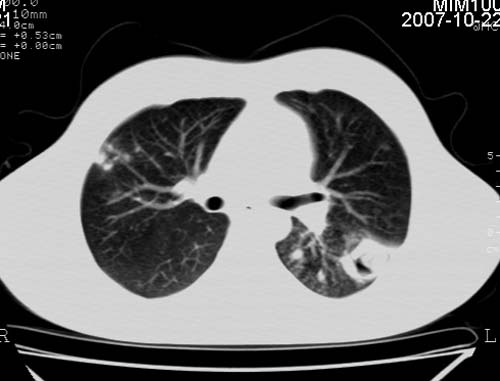

男,21岁,咳嗽、胸闷、乏力伴多汗二十余日、无明显发烧。患者一般情况好,为初三学生。

右肺上叶前段及左肺下叶多形性病变伴厚壁空洞,周边示树芽征.左肺下叶不张改变.

考虑;肺结核,不除外左肺下叶支气管内膜结核.

双肺继发性肺结核伴左侧空洞形成!不除外合并霉菌感染!(双肺多发病灶,左侧病灶形成空洞,并空洞内见壁结节。建议改变体位,观察空洞内结节情况,以便排除霉菌感染!)

左下肺实变能给出合理解释吗?